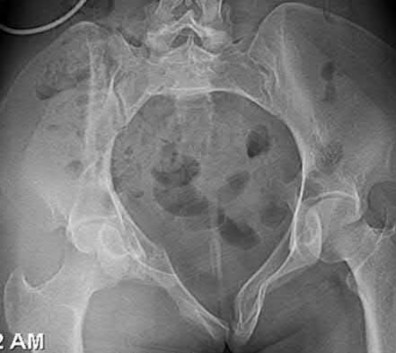

2. # A 35-year-old woman is involved in a head-on collision while driving. Initial radiographs are shown in Figures 8a and 8b. Injury to what vessel increases the risk for osteonecrosis of the injured bone?

5. Artery of the tarsal sinus Corrent answer: 4

The patient has a Hawkins type III talar neck fracture-dislocation with a risk of osteonecrosis ranging from 69% to 100%. Anatomic studies have shown that the artery of the tarsal canal supplies the lateral two thirds of the talar body.

The other vessels listed provide no significant contribution to the talus.